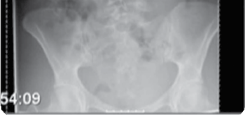

The foundation of successful thoracolumbar surgery lies in exhaustive preoperative planning. Standard imaging protocols must include full-length, free-standing 36-inch orthogonal radiographs to accurately assess global coronal and sagittal balance. The use of EOS low-dose biplanar imaging has become the gold standard, allowing for simultaneous assessment of the spine, pelvis, and lower extremities, which is crucial for identifying compensatory mechanisms such as pelvic retroversion, hip extension, and knee flexion. Magnetic Resonance Imaging (MRI) is mandatory to evaluate the neural elements, assess disc hydration, and identify central, lateral recess, or foraminal stenosis.

High-resolution computed tomography (CT) with multiplanar reconstruction is essential for evaluating bone stock, identifying facet arthropathy, and planning pedicle screw trajectories. In cases of severe deformity or revision surgery, CT-based 3D templating software allows the surgeon to simulate osteotomies, calculate the exact degree of correction required to achieve spinopelvic harmony, and pre-contour rods. The surgeon must meticulously calculate the required Lumbar Lordosis (LL) based on the patient's Pelvic Incidence (PI), plan the upper and lower instrumented vertebrae (UIV and LIV) to avoid ending the construct at the apex of a kyphotic curve, and determine the necessity of pelvic fixation.

Clinical & Radiographic Imaging Archive